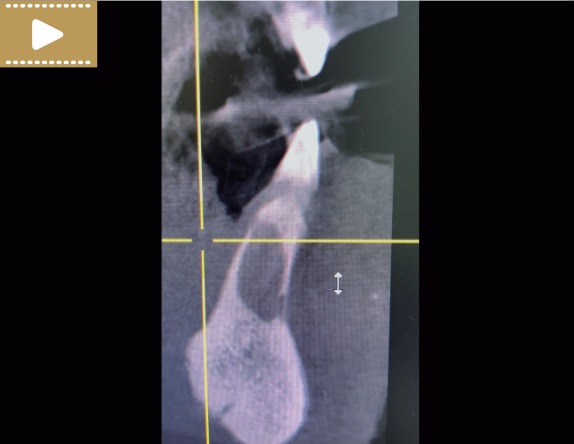

Film 3. CBCT płaszczyzna strzałkowa, zęby 31 i 41 (kwiecień 2021 r.).